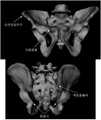

도 14의 좌측은 심각한 골반 불연속성을 갖는 환자의 3차원적 모델 표상이다. 우측에는 좌측에 나타낸 상기 환자의 골반의 3차원적 모델에 대한 일 예가 도시된다.

도 15는 재건된 좌측 모델 및 본래의 환자 모델뿐 만 아니라 우측 및 좌측 인체의 비교이다.

도 16은 재건된 모델과 상기 재건된 골반 모델의 거울 이미지와의 사이의 거리맵이다.

도 17은 완전한 골반 불연속성 및 1.8 mm의 rms 오차를 갖는 재건 결과를 갖는 환자이다.

The left side of FIG. 14 is a three-dimensional model representation of a patient with severe pelvic discontinuity. On the right, an example of a three-dimensional model of the patient's pelvis shown on the left is shown.

15 is a comparison of the right and left human bodies as well as the reconstructed left and original patient models.

16 is a distance map between a reconstructed model and a mirror image of the reconstructed pelvis model.

17 is a patient with complete pelvic discontinuity and reconstruction results with an rms error of 1.8 mm.